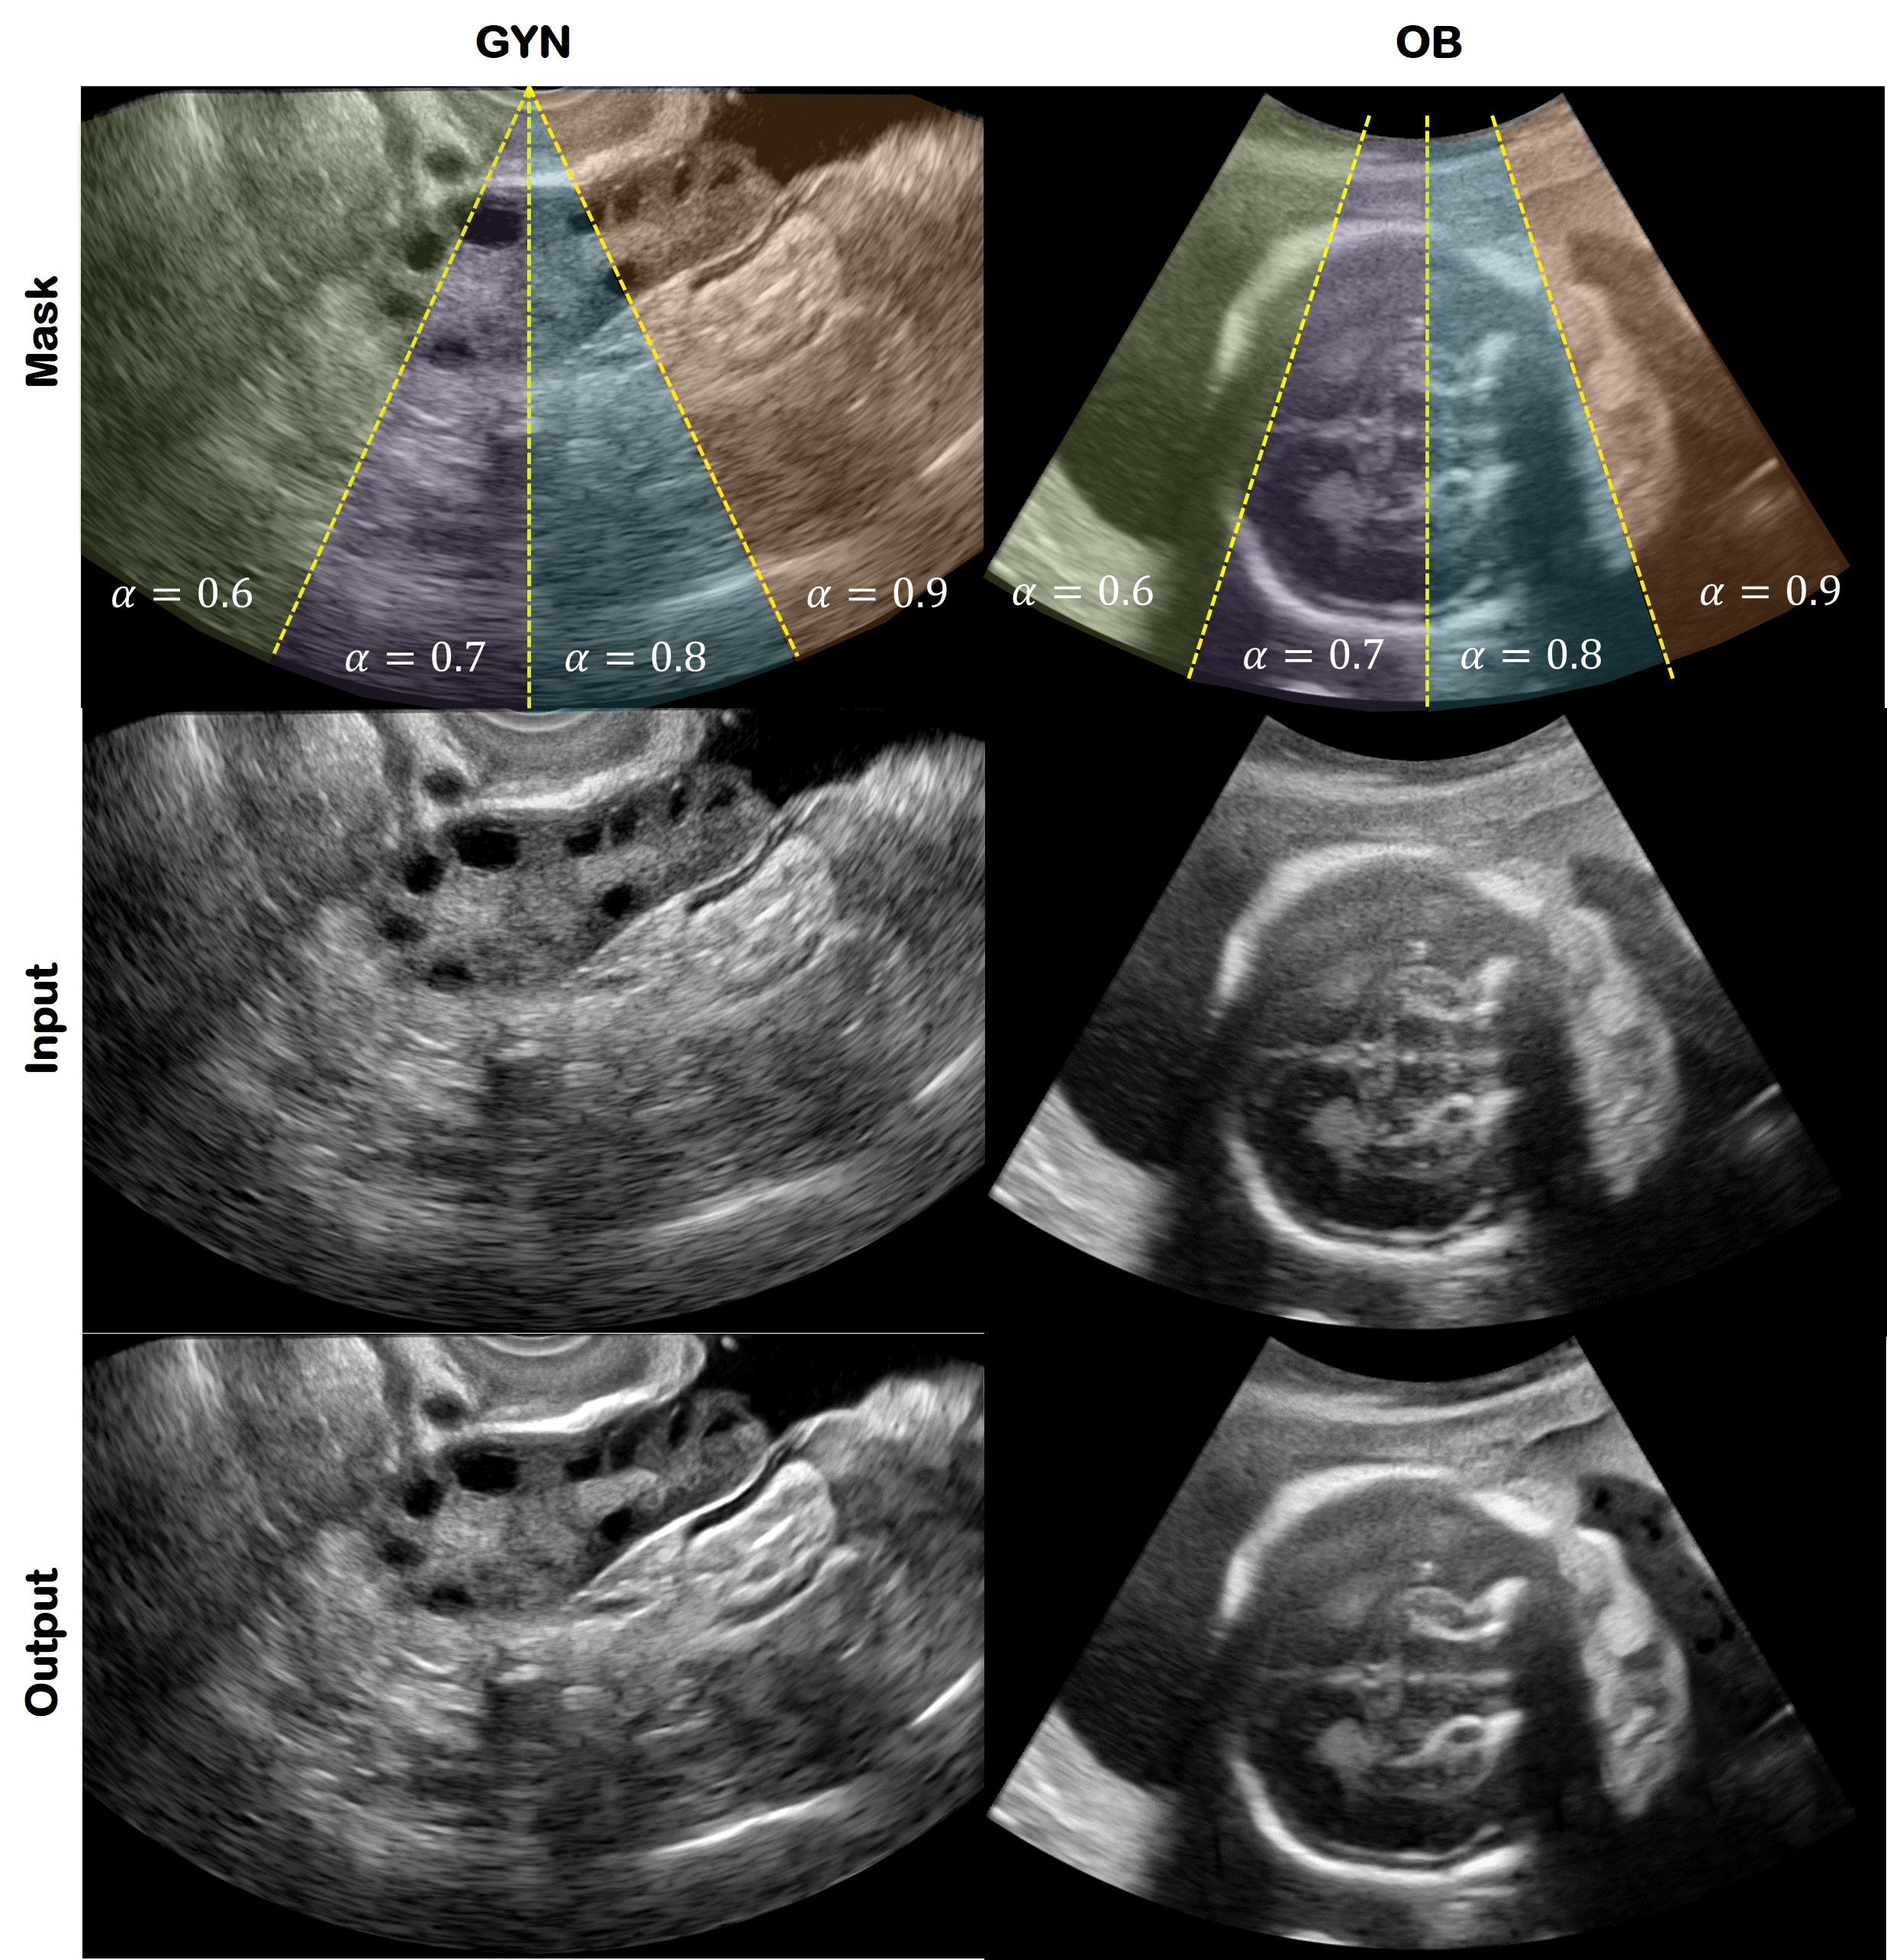

5.2 Spatial Control

Another great advantage of the proposed method is that the user can select the area to be improved. Since AdaIN changes its content feature map using the style statistics generated by the AdaIN code generator, the user can control it spatially. Assume there is a mask like in the first row of Fig. 9. There are four areas marked as green, purple, blue, and orange. Instead of applying the masking procedure four times, our method can easily generate a spatially enhanced image with a single feed-forward process. Specifically, the mask enters the network with the image. Then it is multiplied by the content feature map to normalize only the selected area of with a certain α𝛼\alpha value through AdaIN code interpolation. Accordingly, we can apply four different α𝛼\alpha values to four different regions with a single feed-forward network.

Refer to caption

Fig. 9: Spatial control results. The first row is the mask that shows where and which α𝛼\alpha value was applied. The second and third rows are the input and output, respectively. The first column is gynecology dataset and the second column is obstetric dataset.

As shown in Fig. 9, when the mask area in the top row is applied to each image, the proposed method naturally produces spatially varying quality improvement. This provides more nature views with only enhancing area with diagnostic interest.